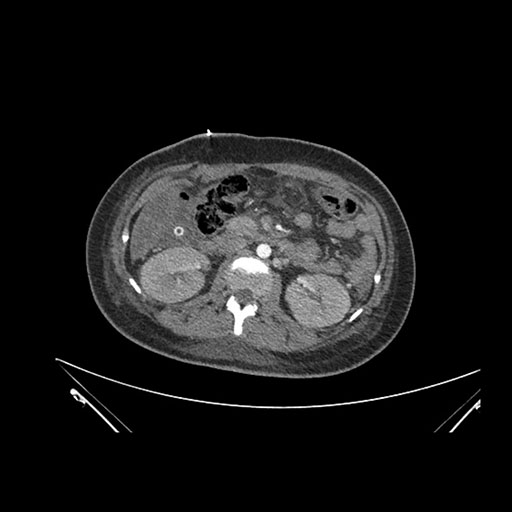

Imaging Analysis

Look through the patient's CT scan to identify any areas of concern for the necessary procedure.

Coronal Arterial

Based on initial findings, which issue(s) would you be most concerned about?